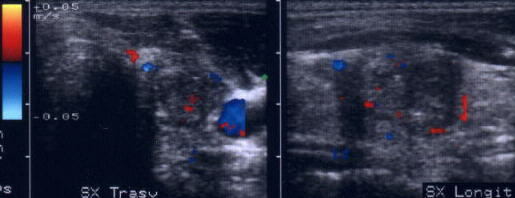

Femeiede 44 ani.

Tireotoxicoza in m. Graves. Tiroida este de dimensiuni normale, dar marcat hipoecogena,

cu contururi difuze, cu arii de striatii hiperecogene de fibroza cronica.

Lob stang, proiectie longitudinala.

Lob drept, proiectie longitudinala.

Acelasi

pacient. La doppler color, vascularizatie bogata, difuza in toata glanda

Femeie de 44 ani. Tireotoxicoza in m. Graves.

Marcata crestere a velocitatii cu picul sistolic (1,44 m/s).